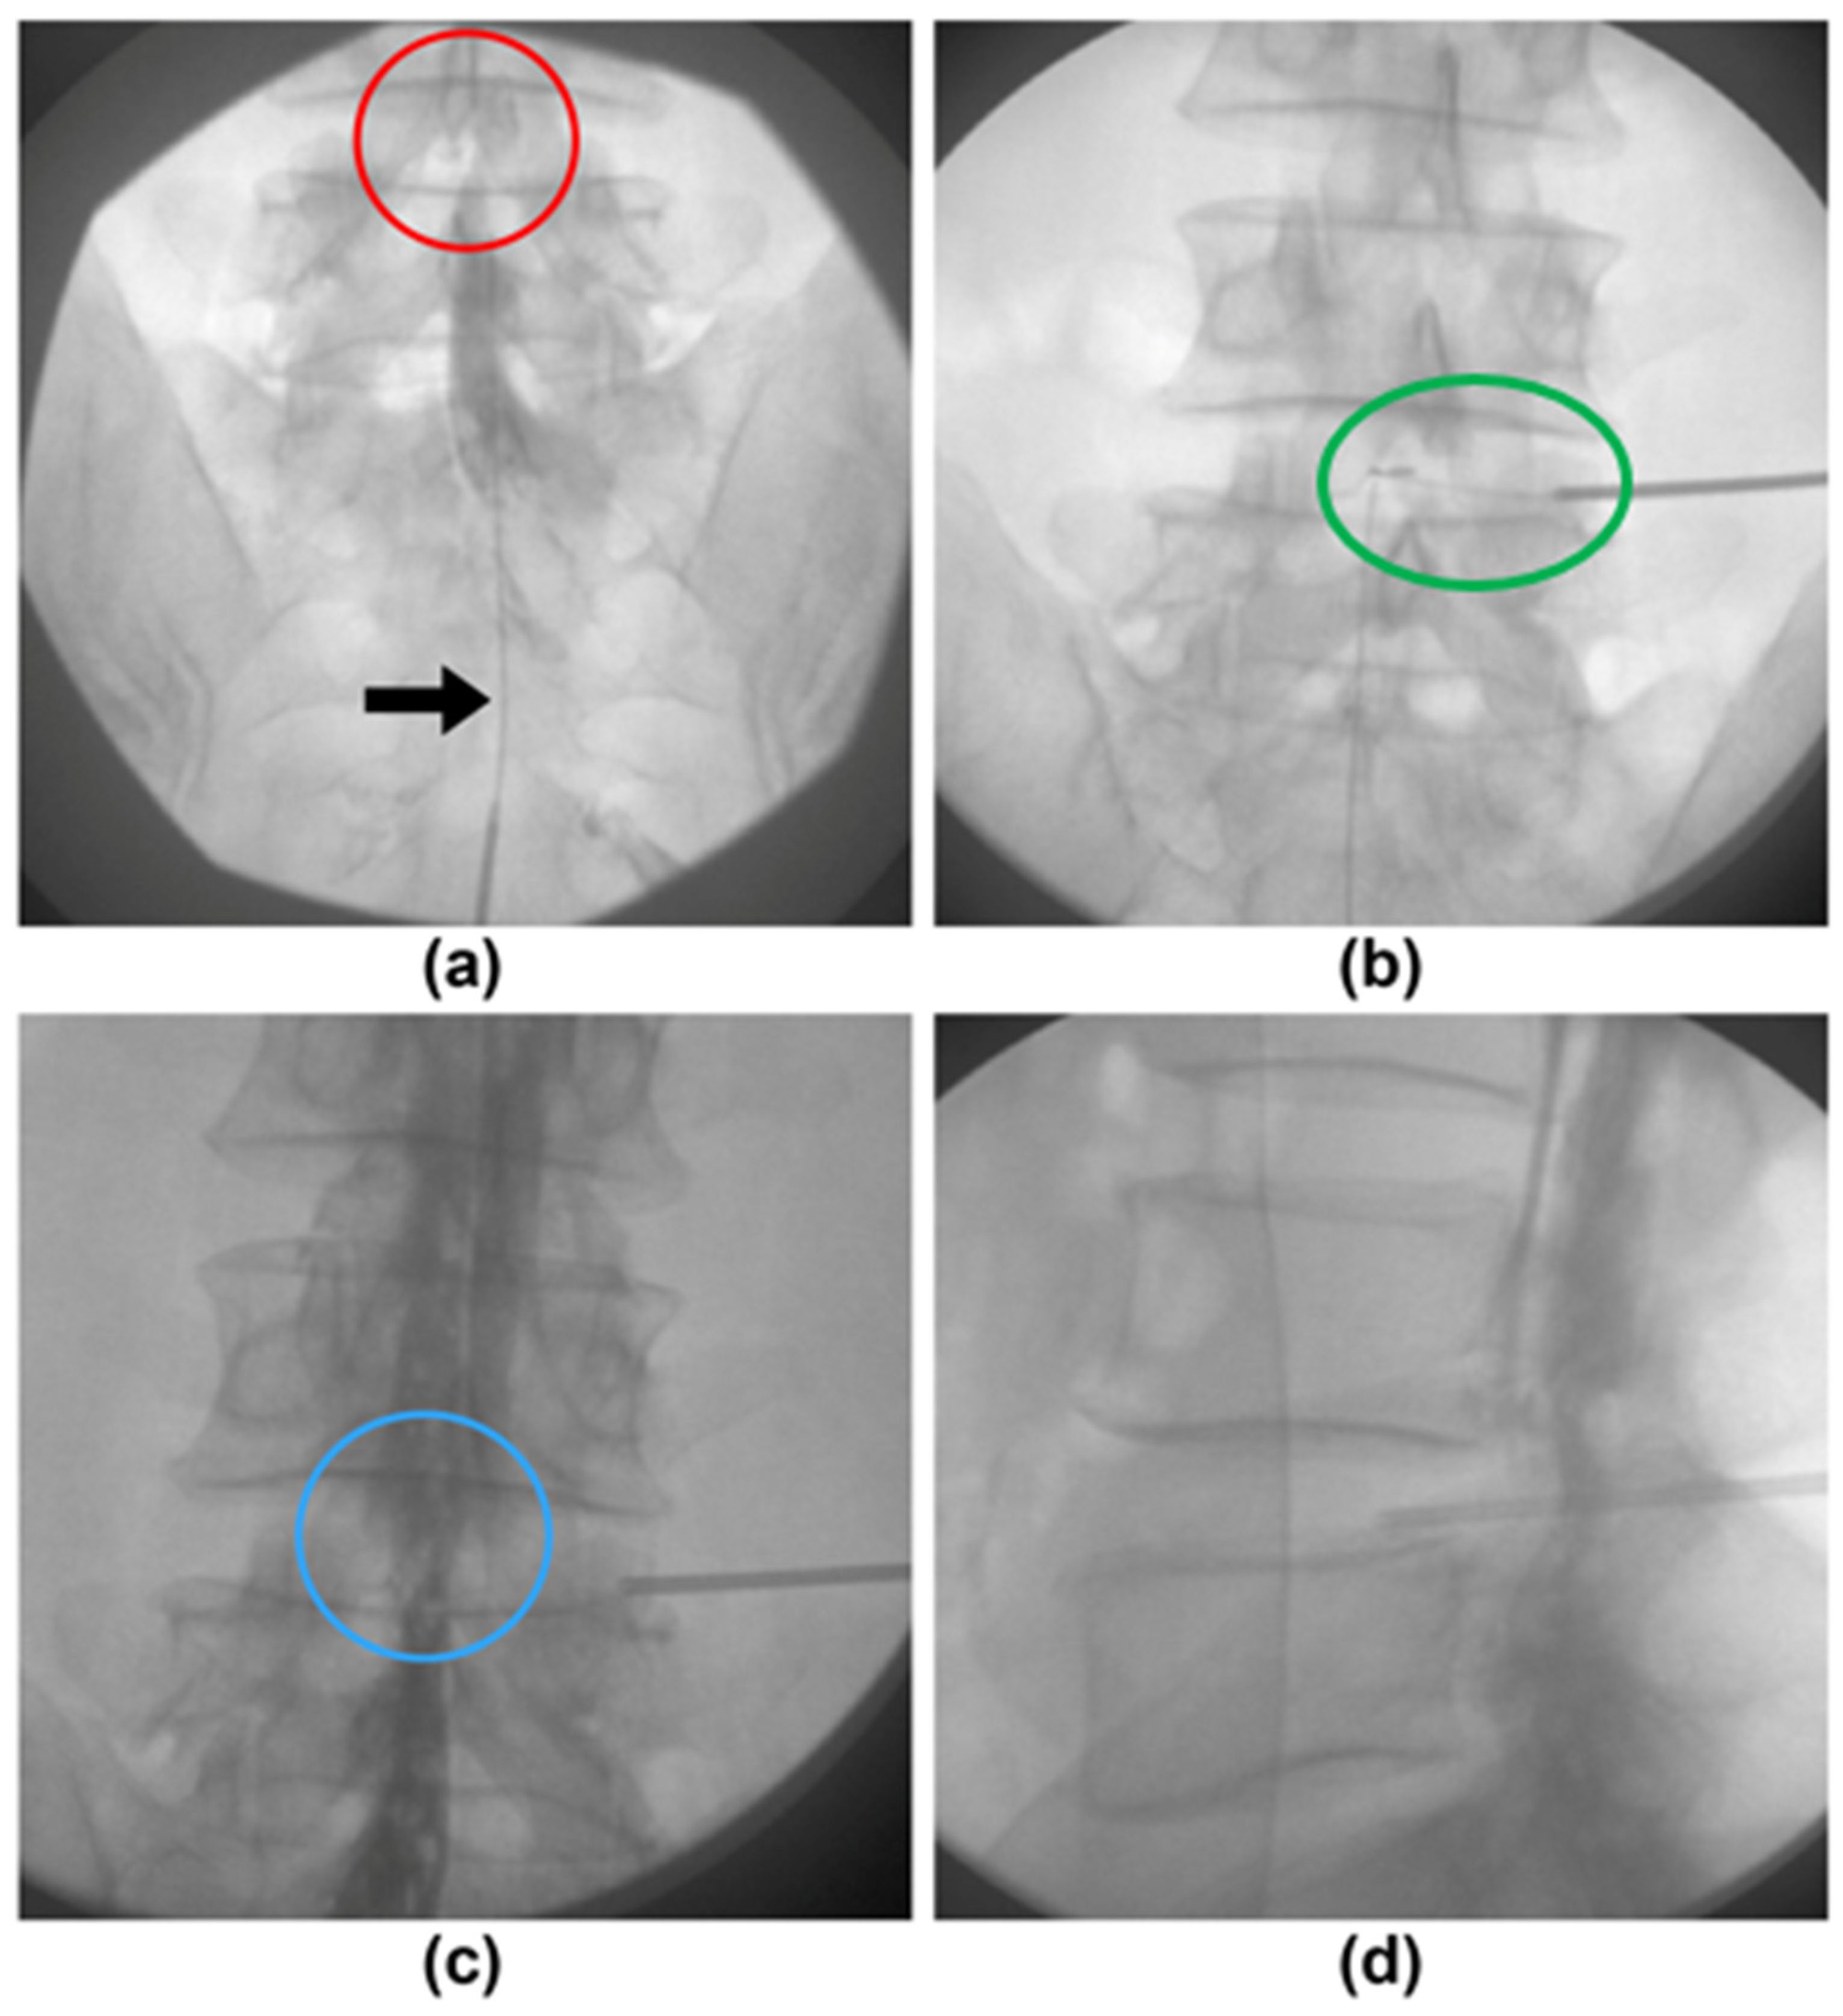

2.2. Percutaneous Plasma Disc Decompression

2.3. Epidurography